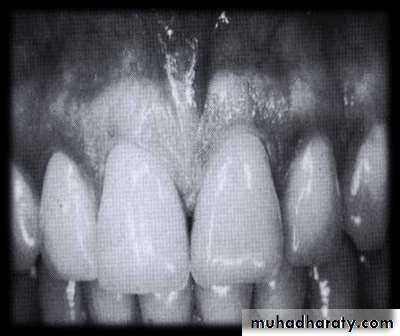

• Extrusion of the maxillary left central incisor and diastema

• associated with a periodontal pocket• Deep periodontal pocket revealed by probing. The probe has penetrated to its entire length.